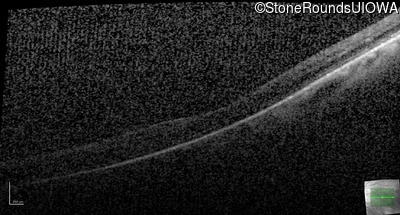

AD Familial Exudative Vitreoretinopathy (IIIE2b)

Age at visit: 32 years